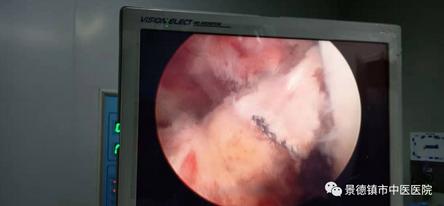

半月板縫合術(shù)后